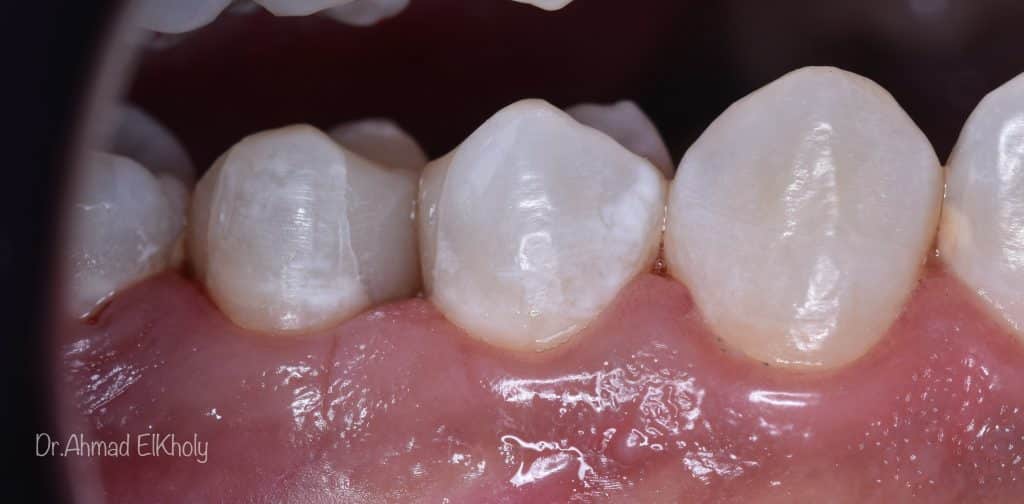

Immediate post op

Contact area

Finished and polished